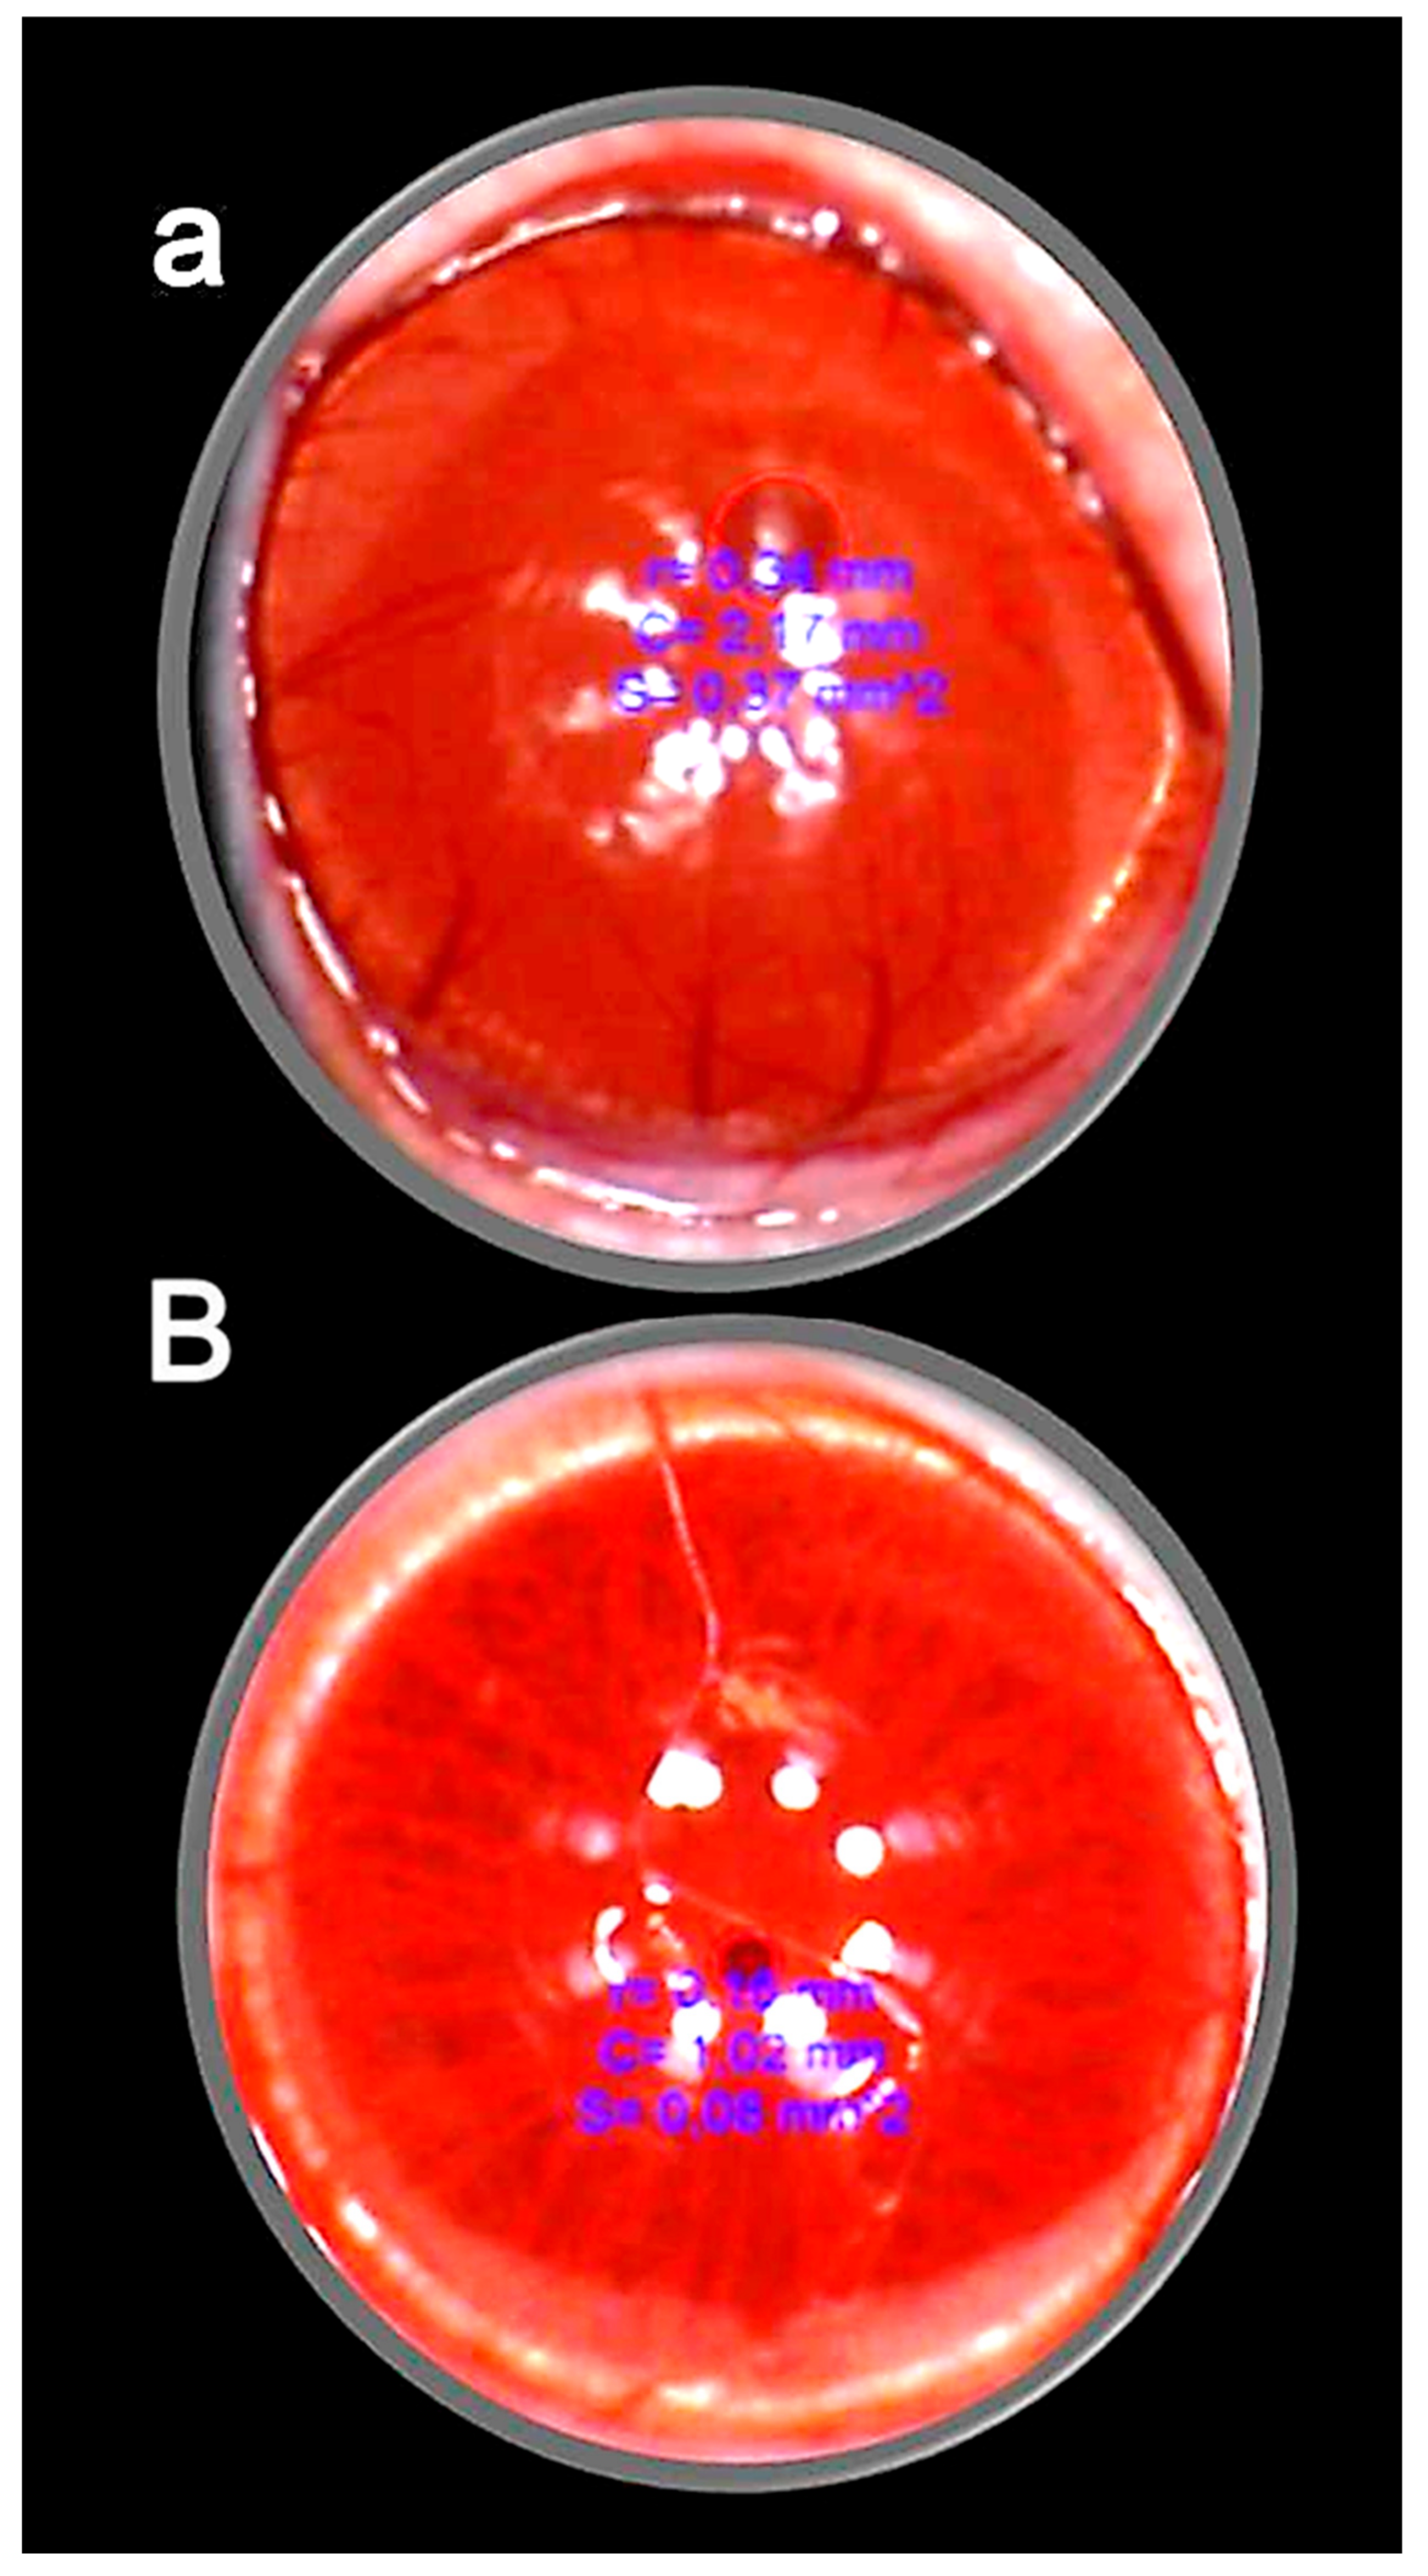

- Kralj, T.; Kokot, A.; Zlatar, M.; Masnec, S.; Kasnik Kovac, K.; Milkovic Perisa, M.; Batelja Vuletic, L.; Giljanovic, A.; Strbe, S.; Sikiric, S.; et al. Stable gastric pentadecapeptide BPC 157 therapy of rat glaucoma. Biomedicines 2021, 10, 89. [Google Scholar] [CrossRef]

- Zlatar, M.; Kokot, A.; Vuletic, L.B.; Masnec, S.; Kralj, T.; Perisa, M.M.; Barisic, I.; Radic, B.; Milanovic, K.; Drmic, D.; et al. BPC 157 as a therapy for retinal ischemia induced by retrobulbar application of L-NAME in rats. Front. Pharmacol. 2021, 12, 632295. [Google Scholar] [CrossRef]